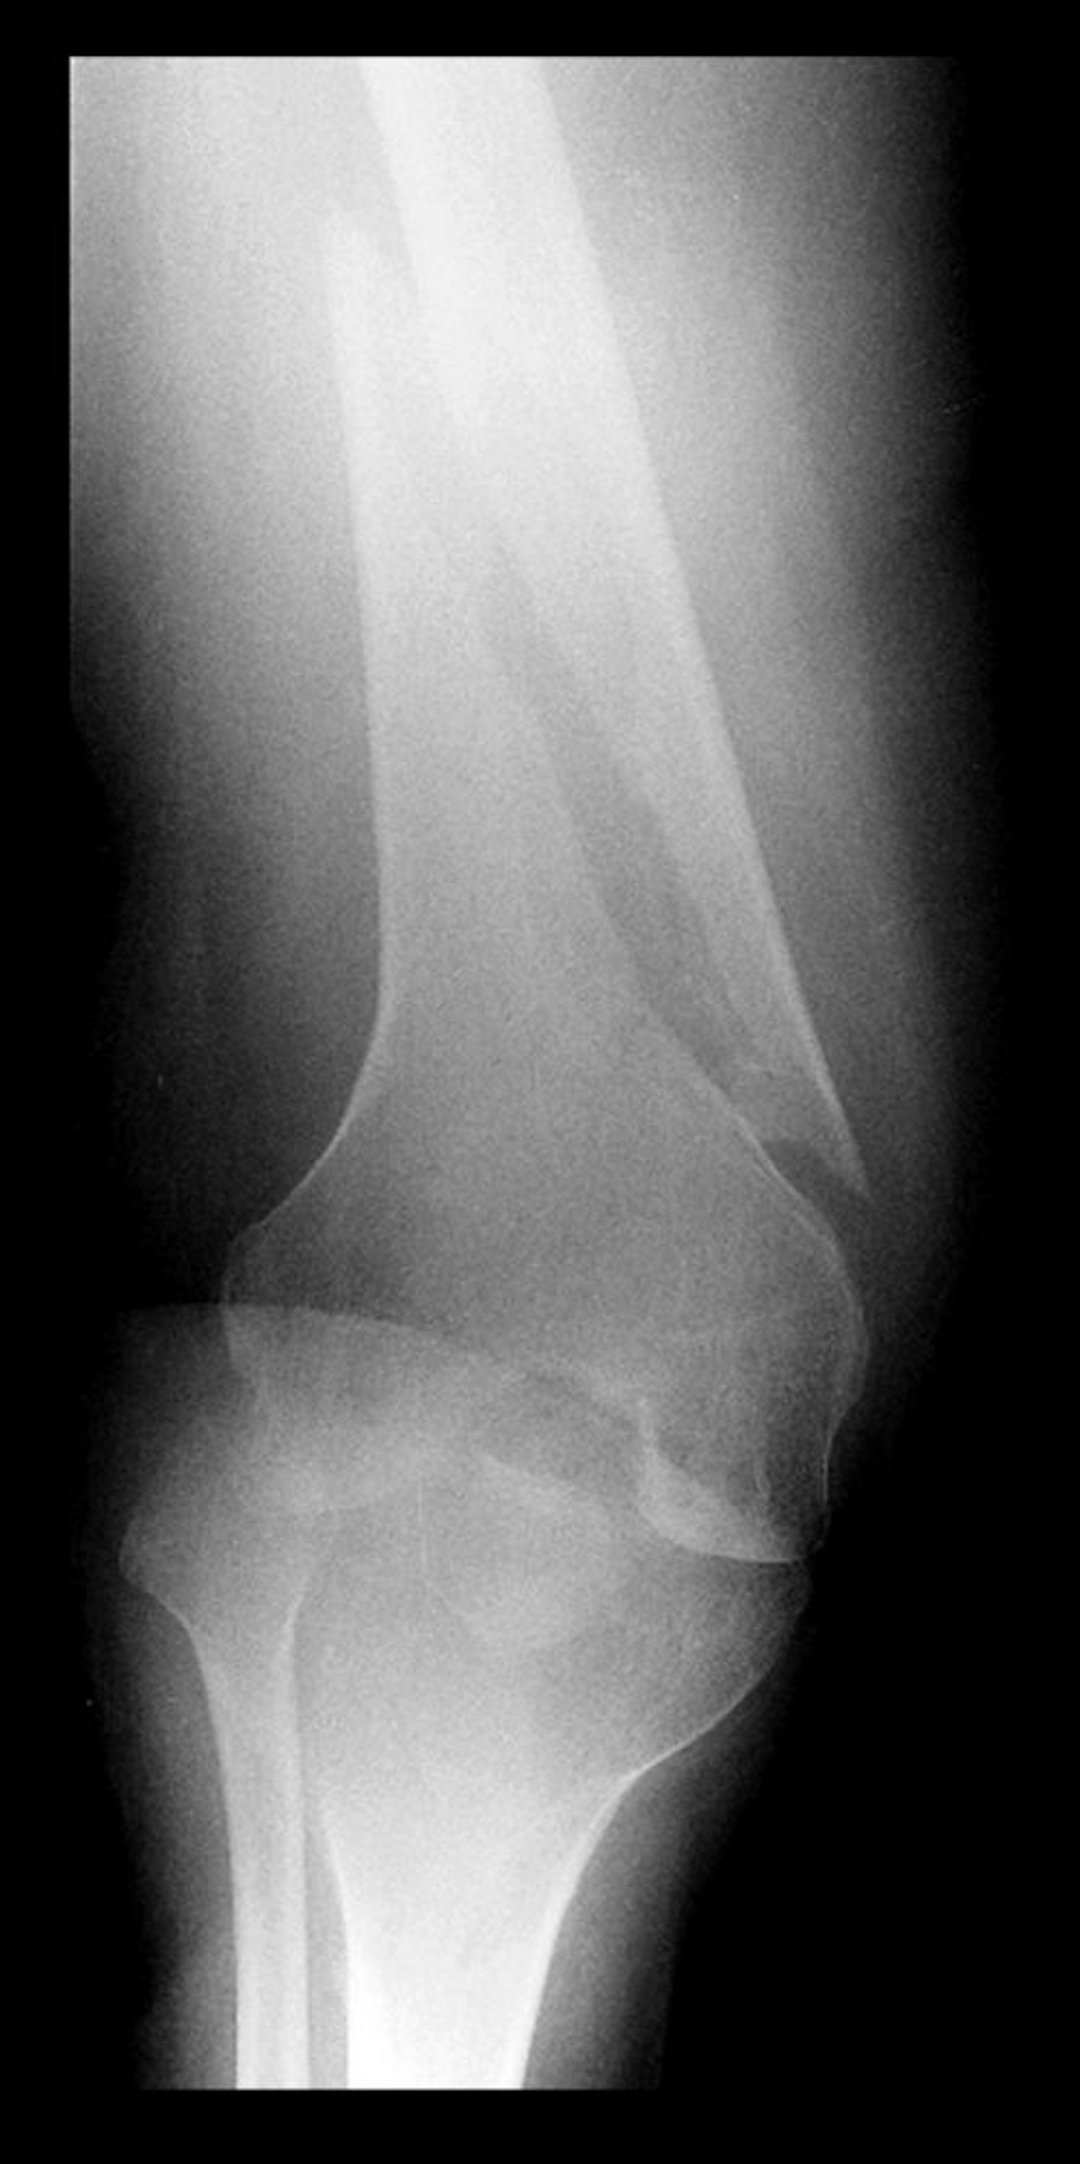

Спиральный перелом дистального отдела бедренной кости

На этой рентгенограмме дистального отдела бедренной кости имеется просветление, расположенное параллельно длинной оси кости, что указывает на спиральный перелом.